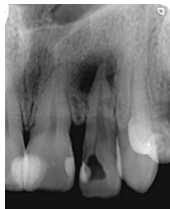

Radiográficamente se pudo observar una lesión radiolúcida de tamaño considerable a nivel apical, con pérdida ósea.

Características radiográficas

Figura 1: Radiografía inicial del órgano dentario 1.2 Se evidencia la apertura de la cavidad pulpar, afectación ósea y una lesión radiolúcida en el ápice. Fecha: 30/06/2022

Fuente: Dra. Karina Tito, 2022